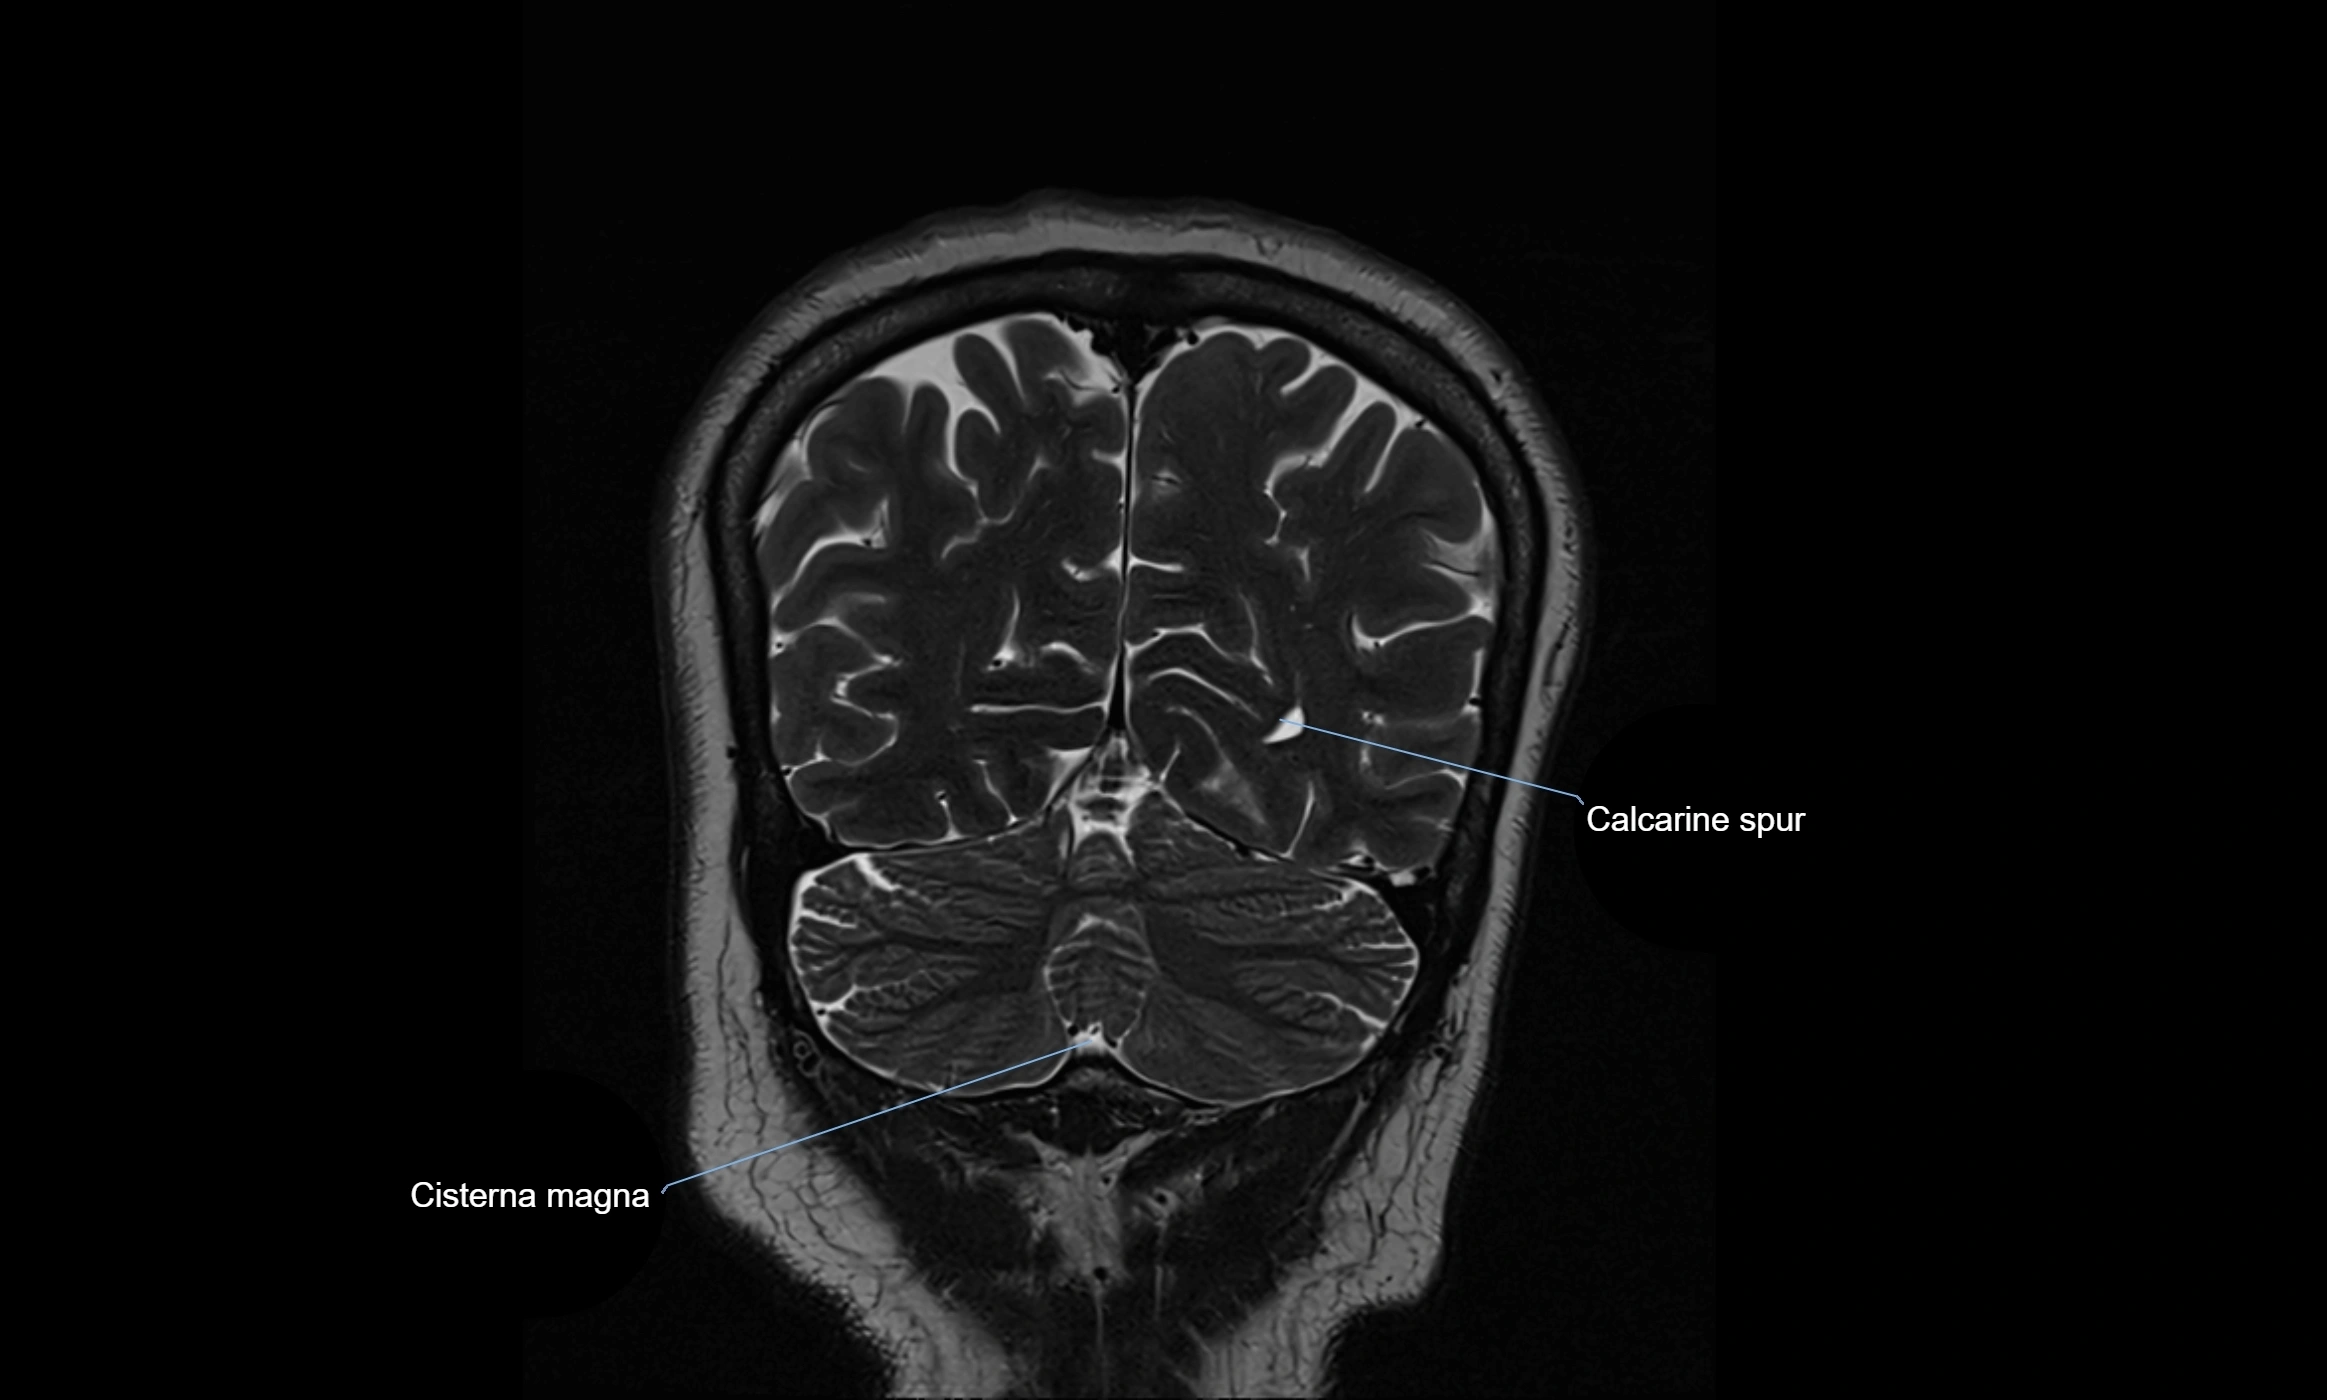

MRI images

image